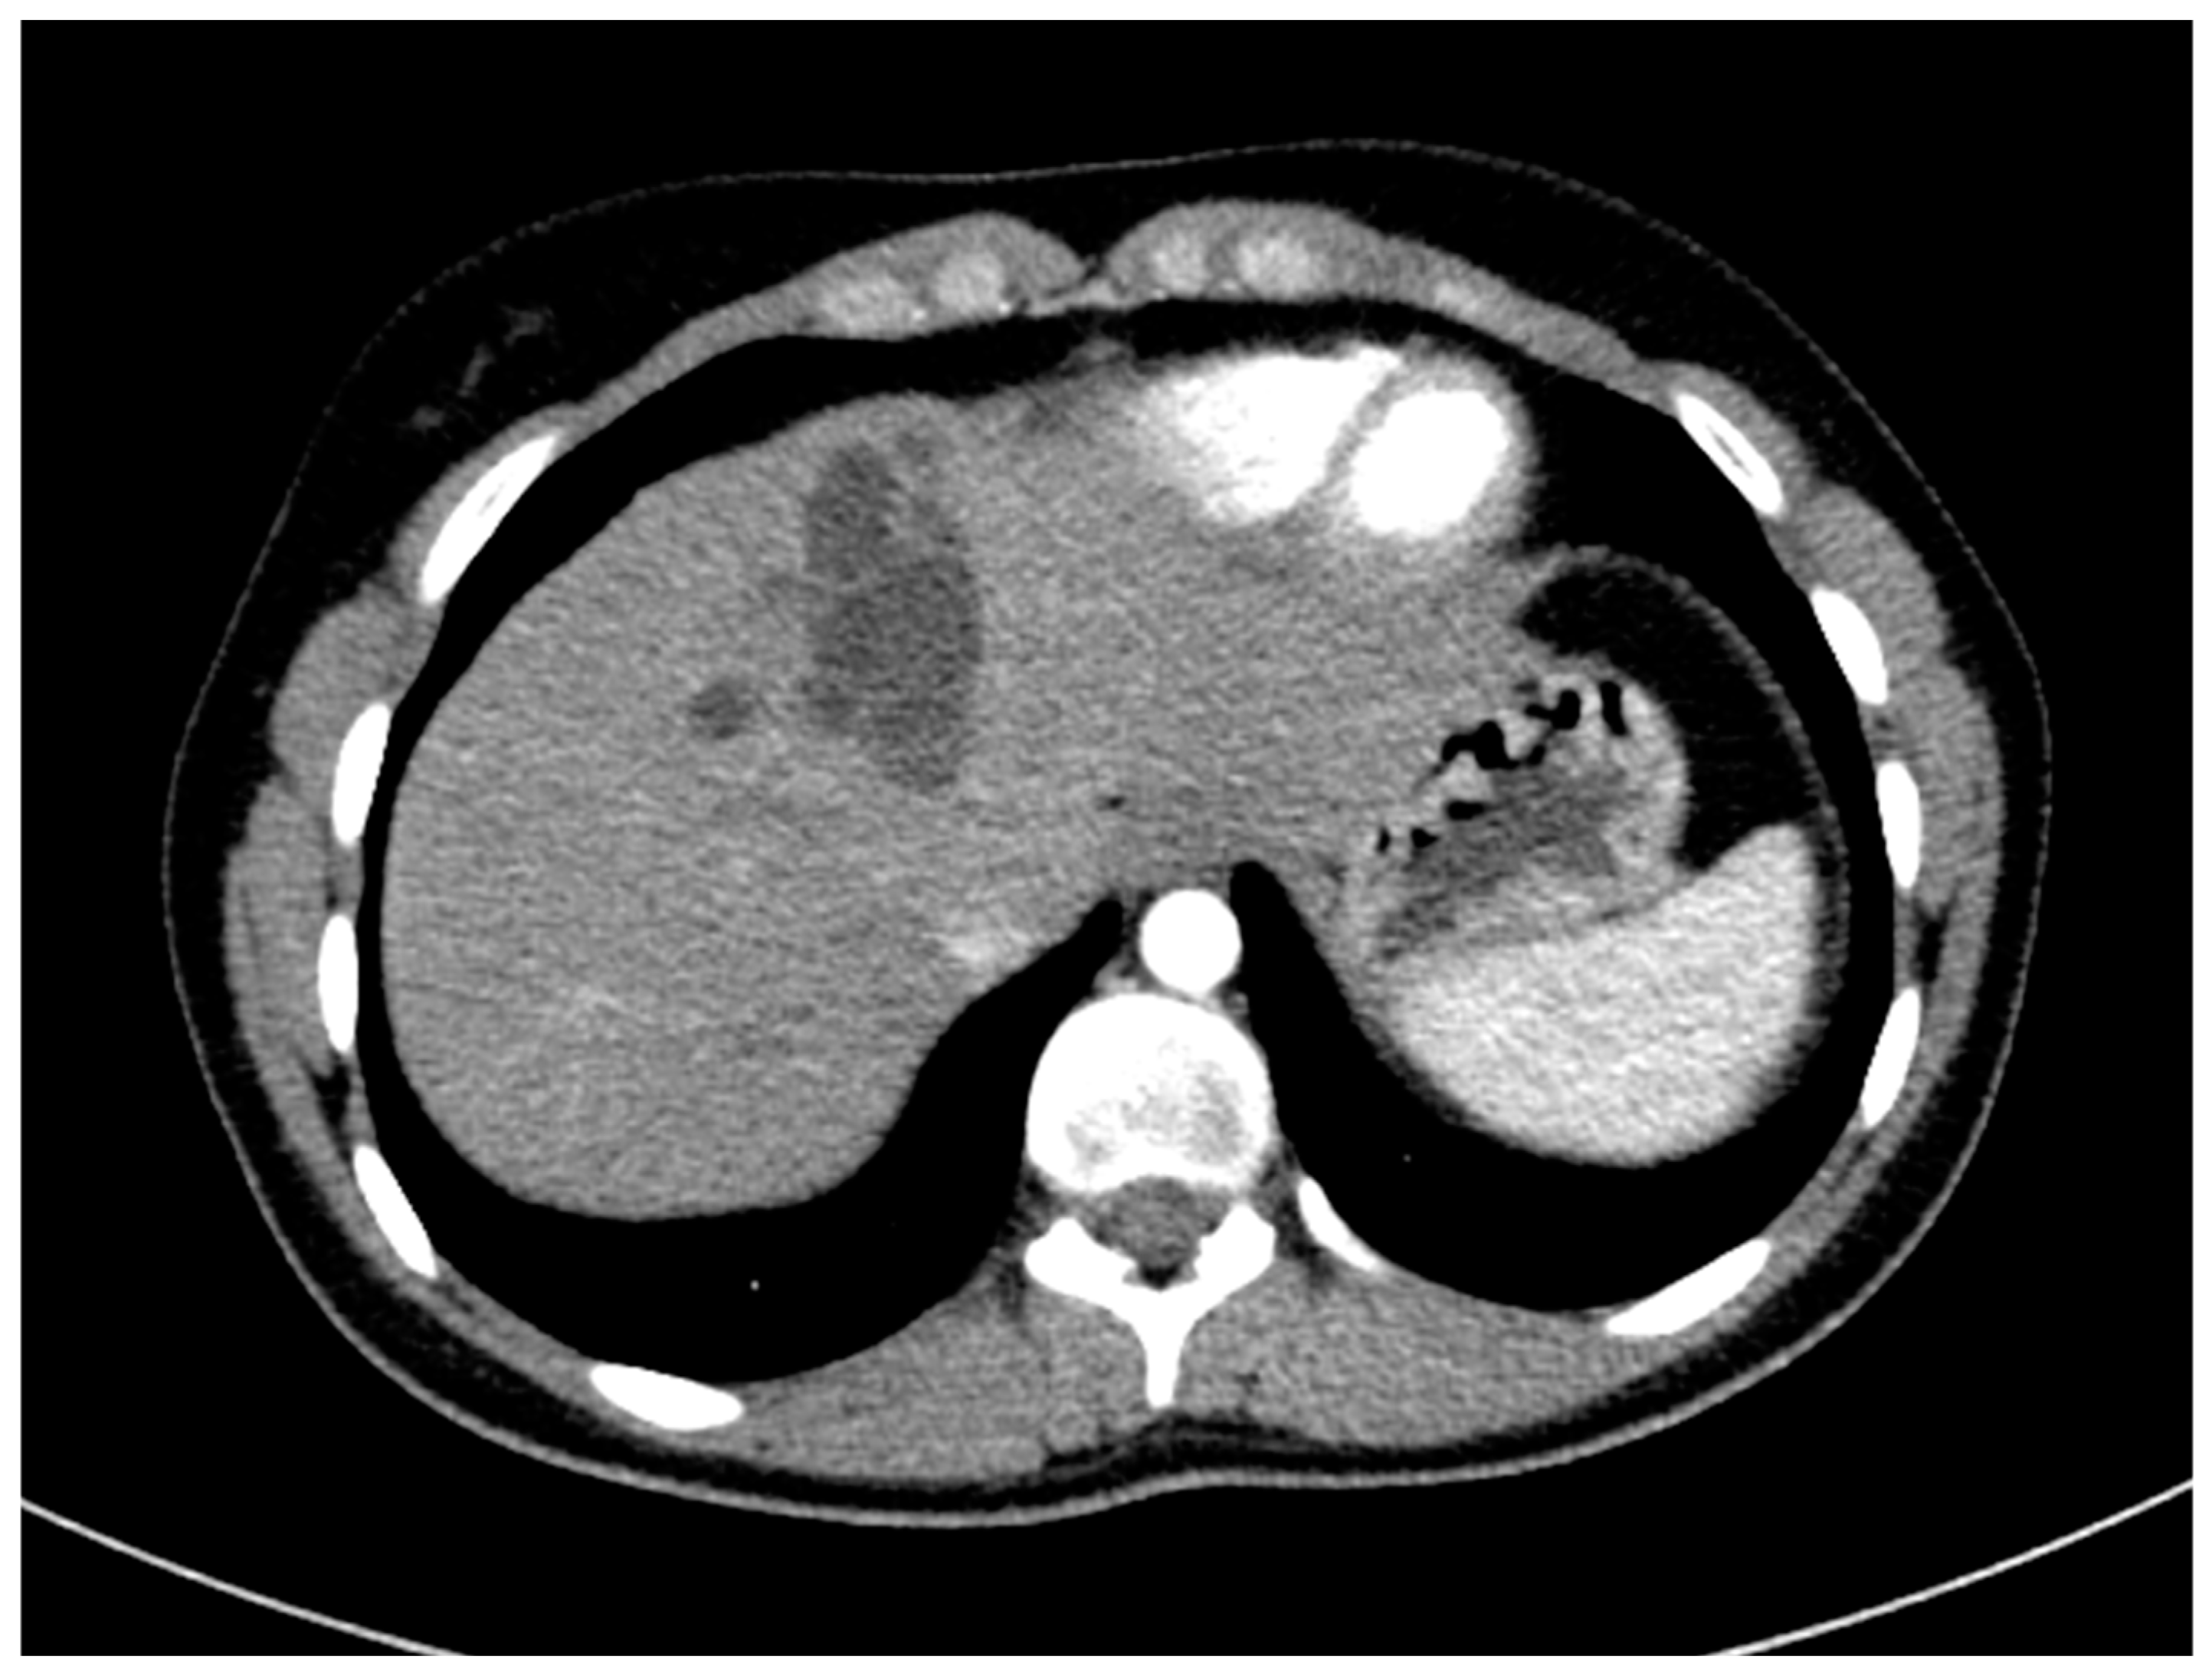

The surgical department decided not to opt for a surgical resection due to difficult access to the cyst, and therapy with the antihelminthic medication albendazole for four weeks was initiated. Additional diagnostics, including chest CT and an MRI scan of the brain, did not find any further extrahepatic manifestations of the hydatid disease. The chest CT scan included parts of the abdomen and also depicted the cyst and lower-attenuated daughter cysts (Figure 6).

Figure 6.

CT imaging shows a large hydatid cyst in segment IV, classified as WHO type CE2. The main cyst has slightly higher attenuation compared to the smaller peripheral daughter cyst.

CT scanning, with its high sensitivity and specificity, is an effective method for describing rupture, infection, calcification, and extrahepatic spread [2,5,7]. On the other hand, MRI scanning is a modality of choice for biliary complications [2]. CT scans depict air–fluid levels in cases of infection or perforation into the hollow viscera. It is a modality of choice in cases of peritoneal seeding, because it enables the imaging of the whole abdomen [7]. CT scanning is not suitable for the staging of hydatid disease. Furthermore, a finding from CT and MRI scan, that helps to rule out CE, is internal enhanced septa [2]. On the contrary, specific signs of the disease are daughter cysts and an internal detached membrane [15].